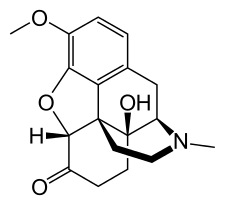

- Hydrocodone

Hydrocodone Hydrocodone |